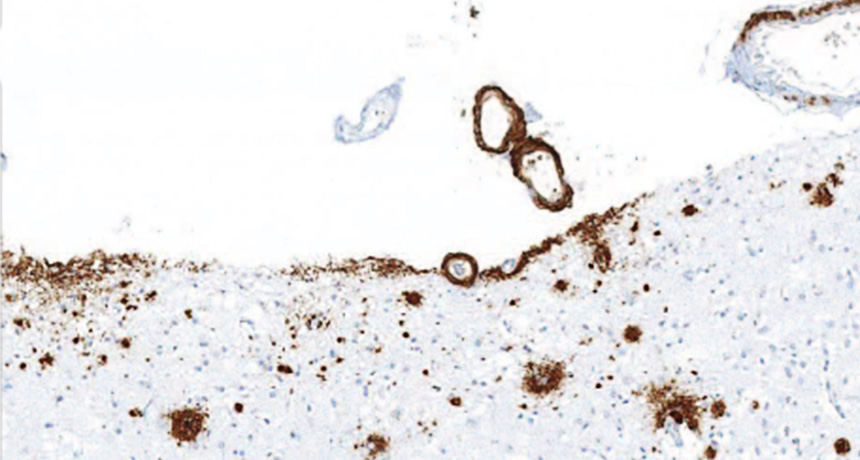

BUILDUP  Amyloid-beta (brown) accumulated in the front of the brain in a person who received injections of cadaver-derived growth hormone as a child, suggesting that the injections were contaminated with A-beta.

Z. Jaunmuktane et al/Nature 2015